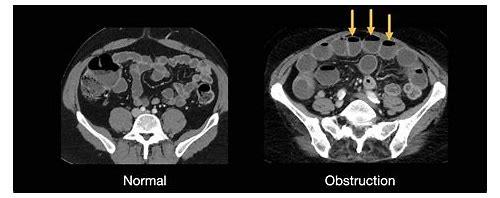

计算机断层成像(CT)通过X射线束对人体进行多角度扫描,利用不同组织对射线吸收的差异重建出精细的横断面图像,这种技术虽能精准诊断疾病,但其本质仍属于电离辐射范畴,单次头部或胸部CT的辐射剂量约为2-10毫西弗(mSv),而腹部/盆腔部位的检查因靠近生殖器官,局部累积量更高,对于普通人群而言,偶尔接受一次CT通常不会造成急性伤害;但对于正处于生殖细胞活跃期的备孕人群来说,情况则截然不同。